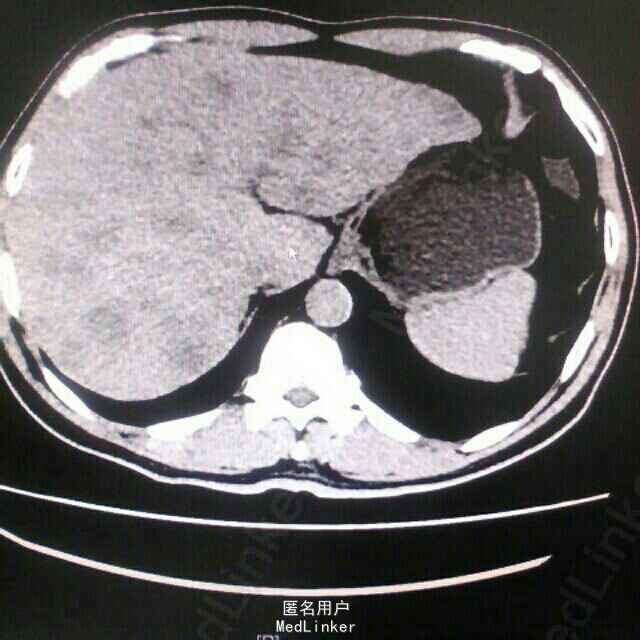

入院后查全腹部CT示:回盲部升结肠癌,累及浆膜层,周围多发肿大淋巴结,肝多发转移瘤(相当壮观,亲们点开图感受一下),肠镜下升结肠肿物活检病理示:中~低分化腺癌,Ki-6780%+.

考虑诊断“结肠癌肝多发转移”,与送检RAS基因,回报示:RAS基因突变野生型。遂予爱必妥(西妥昔单抗)+FOLFOX方案化疗7程。4程后复查胸腹部CT提示肿瘤明显缩小,评价疗效PR(部分缓解)。7程后复查肝内转移瘤增多增大,考虑进展,遂改用安维汀(贝伐单抗)+FOLFIRI方案化疗2程,2程后复查肿瘤标记物升高,且患者腹较前明显,肿瘤有进展趋势,考虑患者靶向药物及化疗疗效短暂,考虑原发耐药可能,且患者一般情况较前变差,KPS评分70分,癌痛明显。